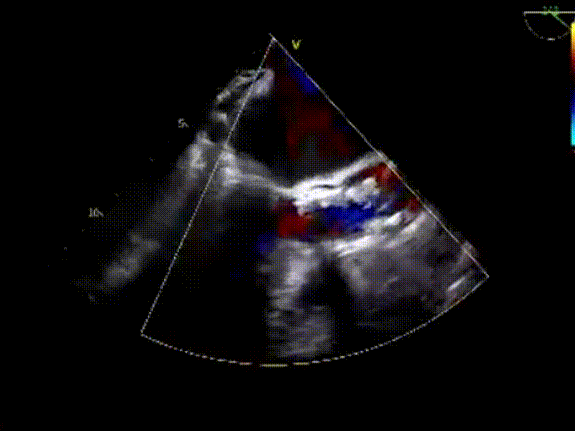

术后即刻超声评估